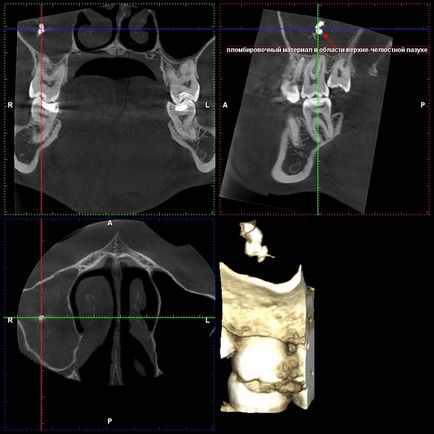

Kitöltő anyaggal az arcüreg